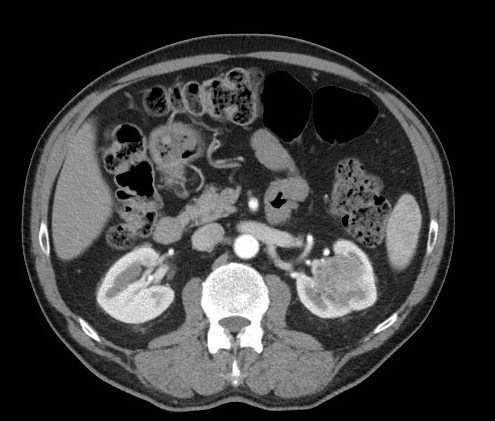

CT: masa renal izquierda, solida, ligeramente heterogénea de aproximadamente 39 x 36 x 27 mm, localizada fundamentalmente en seno renal de polo superior con pequeña afectación de la cortical. No adenopatías patológicas. No trombosis de vena renal ni alteraciones anatómicas vasculares. Ante estos hallazgos se propone tratamiento quirúrgico con nefectomía total.